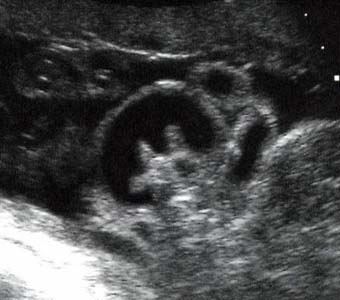

Lèvre supérieure